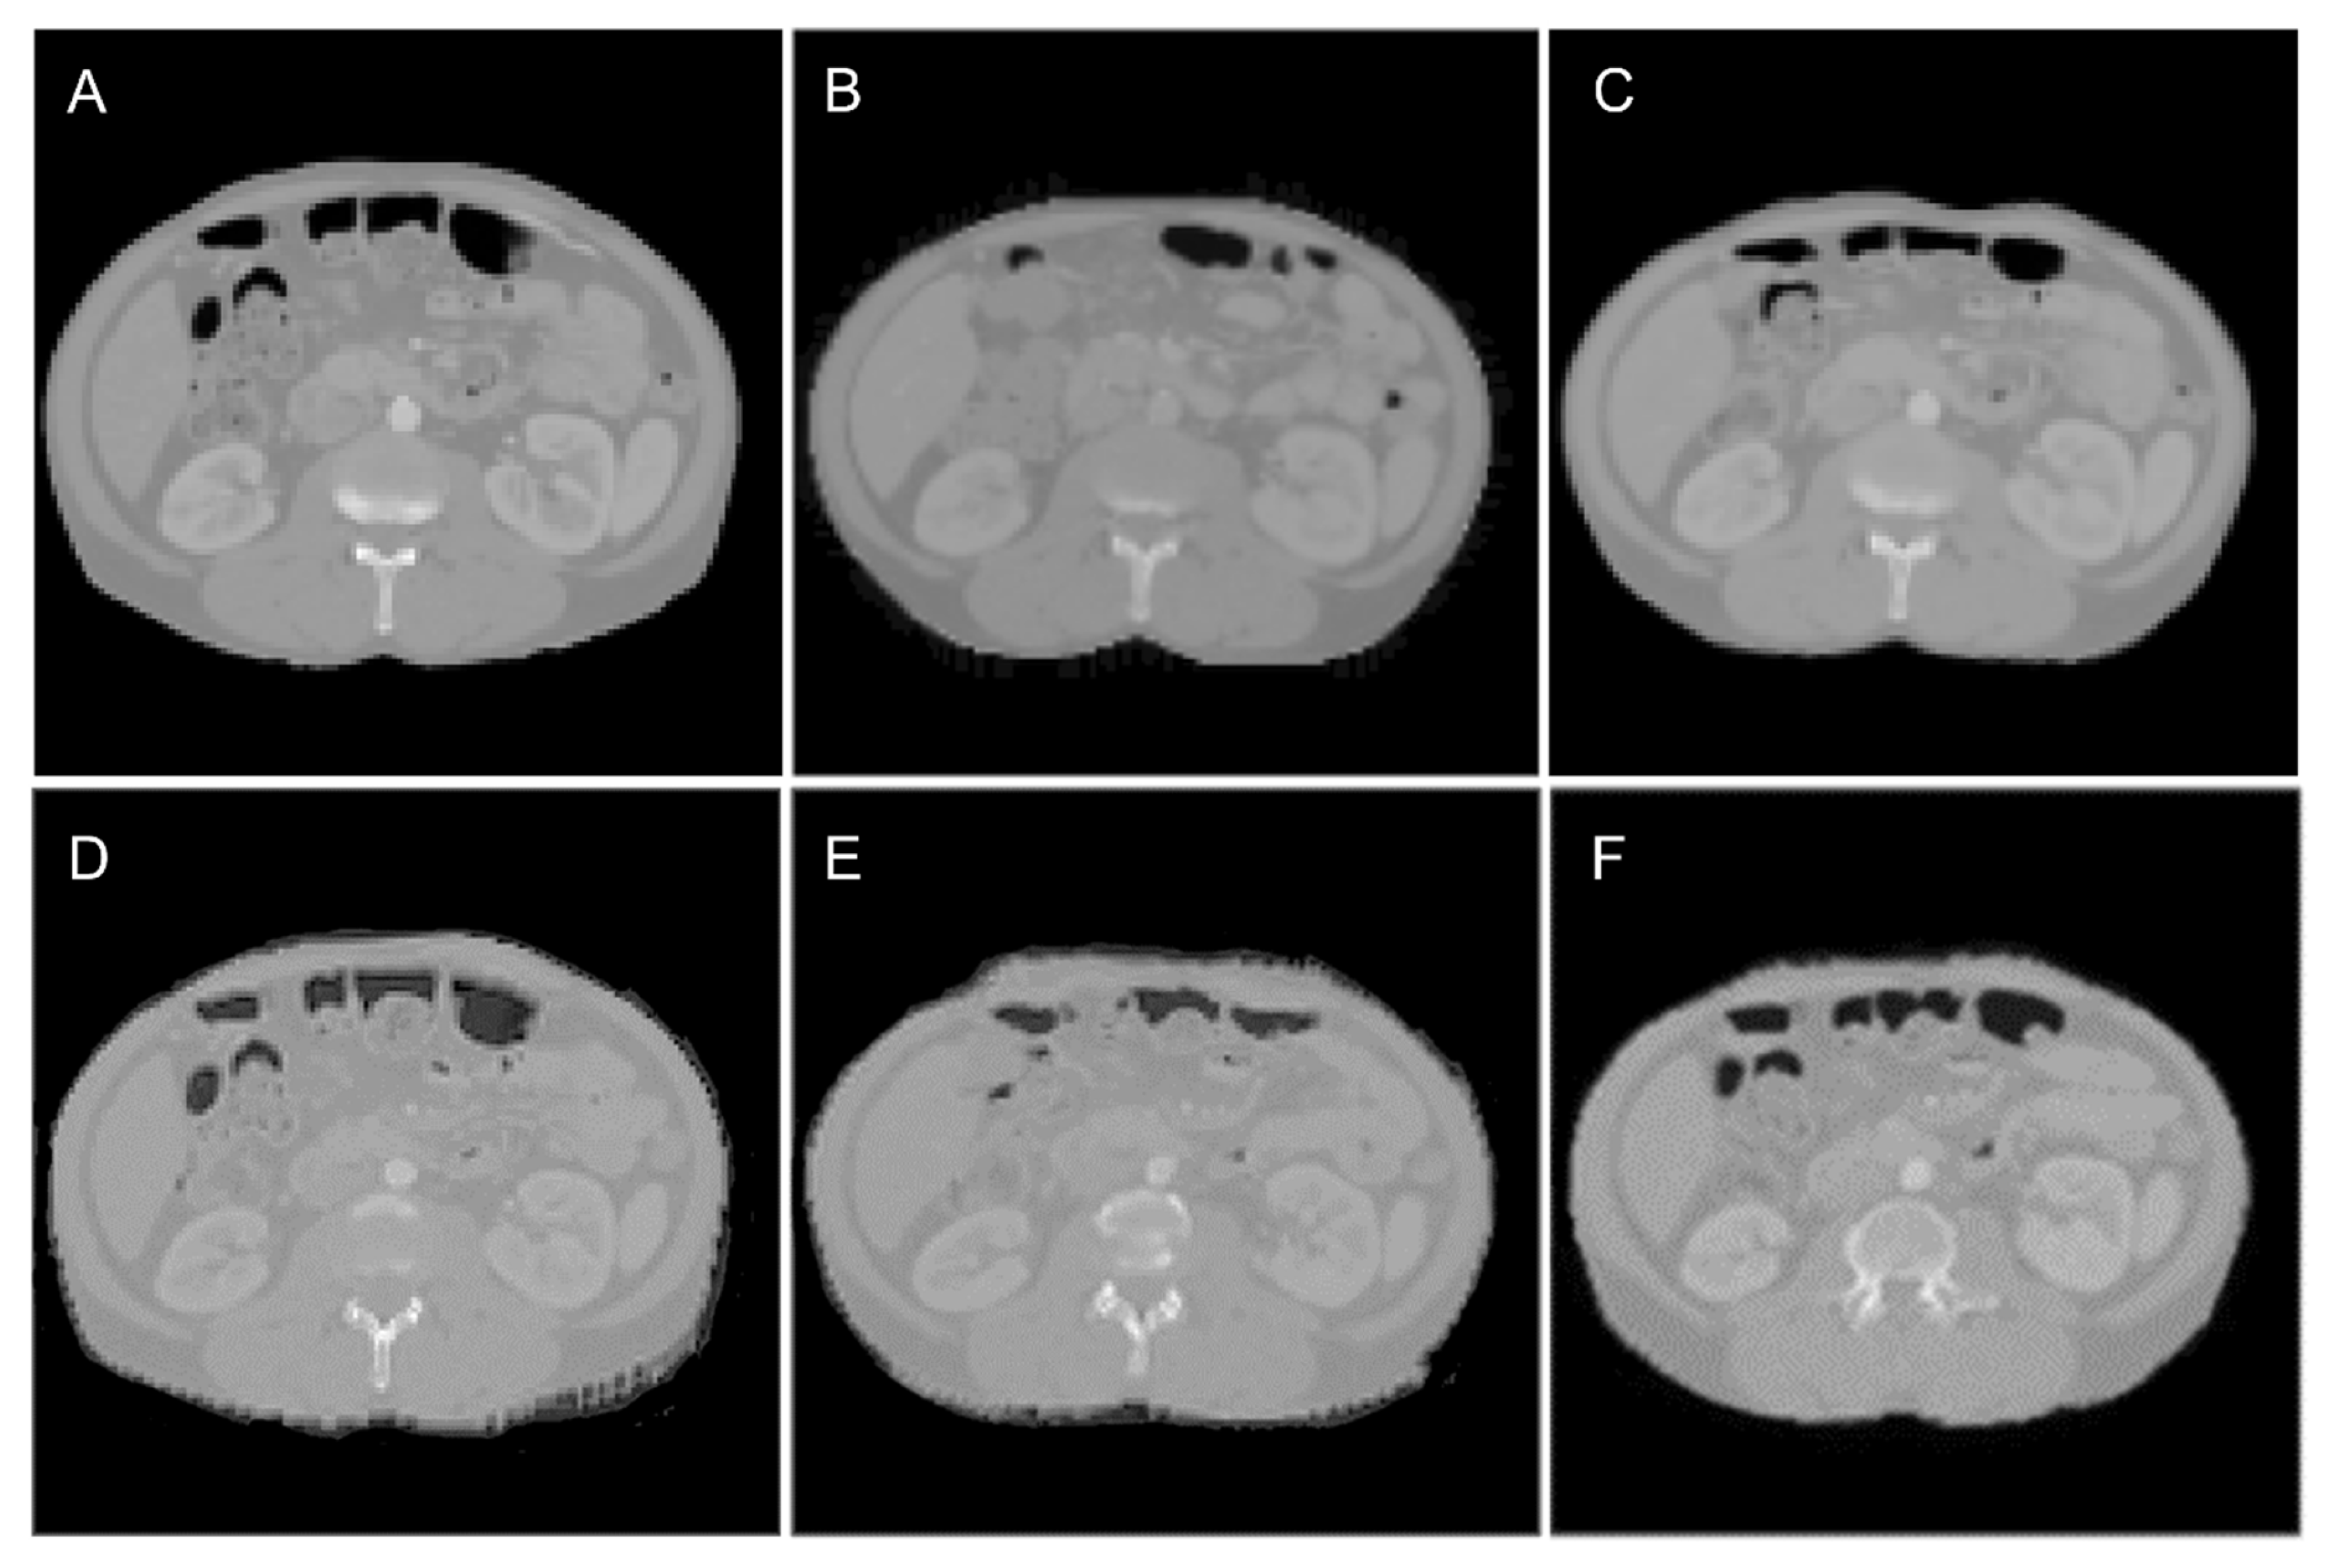

2.2. Deep Learning Model

2.3. Training and Testing of the Model